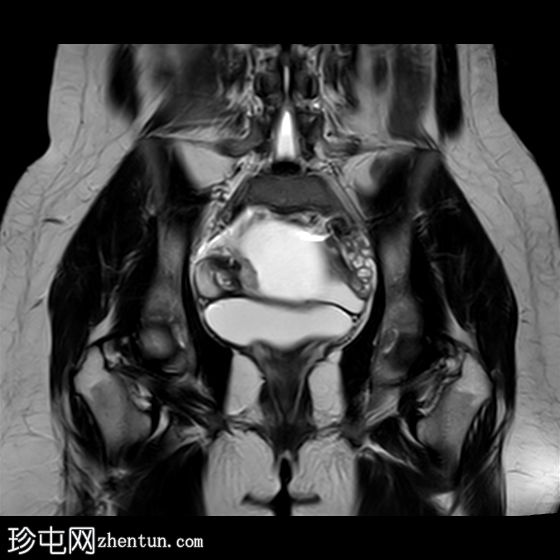

冠状位

T1加权像

右侧卵巢增大,卵泡呈周边排列。

附件血管蒂扭转(漩涡征)。

右侧附件旁可见一较大的、边界清晰的盆腔囊性病变,向右倾斜,提示为卵巢旁囊肿。

本病例展示了卵巢扭转的典型影像学特征,包括卵巢增大、卵泡呈周边移位、卵巢向内侧偏移以及特征性的漩涡征。

在这种情况下,较大的卵巢旁囊肿被认为是发生卵巢扭转的高危因素。如果卵巢旁囊肿较大(>5厘米)或活动度较大,其重量/活动度增加会牵拉附件,导致卵巢和输卵管发生扭转。